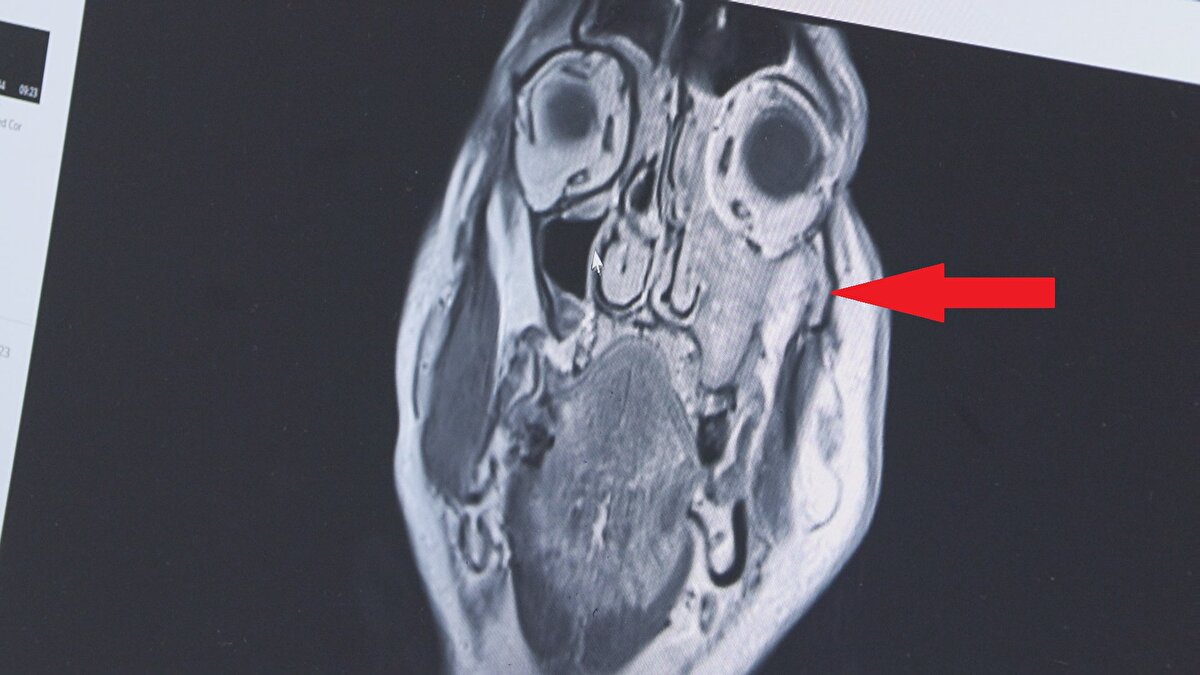

Yanağında sertlik ve ağrı şikayetiyle Kastamonu'da diş hekimine giden Erol Tekin'e (55) önce apse olduğu düşünülüp antibiyotik tedavisi verildi. Tedaviye rağmen ağrı ve sertlik geçmeyince bu kez Akyazı'daki oğlunun diş hekimine gitti. Sol üst dişi de sallanmaya başlayan Tekin'e yapılan biyopsi sonucu, yanağındaki kitlenin nadir bir kanser türü olduğu anlaşıldı. Çok tehlikeli bir bölgede tümörü olduğu anlaşılınca rotayı İstanbul'a çeviren Erol Tekin, acilen ameliyata alındı. Sol göz altından boynuna kadar uzanan bölge, tümörden temizlendi. Prof. Dr. Apuhan, “Çok sinsi ilerleyen bir tümör. 1 ay daha geç kalsaydı sol gözünü de almak zorunda kalacaktık" dedi.

Prof. Dr. Apuhan, "Maksiller sinüs tümörü olarak adlandırılan bu tümör çok nadir görülür. Genellikle sinüzit veya diş ağrısıyla karıştırıldığı için sinsi ilerler ve geç teşhis edilir. Hastamız 1 ay daha geç kalsaydı sol gözünü de almak zorunda kalacaktık. Tümörü komple temizledik. Radyoterapi ile tedavisi tamamlanacak ve yanak içine protez konarak kozmetik düzeltme de yapılacak" dedi. Uzun süren tek taraflı burun tıkanıklığı ve kanaması, yanakta kitle olduğu durumlarda bu açıdan da hasta değerlendirilmeli" dedi. Tekin'in 34 yıllık eşi Hülya Tekin ise yaşadıklarını anlatırken gözyaşlarını tutamadı eşinin, 4 ay sonra doğacak ilk torunlarını kucağına alabileceği için çok mutlu olduğunu söyledi.

Prof. Dr. Apuhan, şu bilgileri verdi: "Hastamız diş yakınması nedeniyle başka bir merkezde diş hekimine gidiyor. Oradan bize yönlendirildi. Endoskopik olarak muayene ettik ve burnun sol tarafında bir kitle ile karşılaştık. Daha sonra yaptığımız görüntüleme tetkiklerinde yüzün sol tarafında maksiller ve etmoid sinüs dediğimiz bölümü dolduran, göze ve beyin dokusuna kadar uzanım olan bir kitleyle karşılaştık. Ameliyatta özellikle sol tarafta damak bölgesinin göze ve beyne yakın bölgelerini de temizledik. Gözü koruduk. Tümörün geliştiği anatomik bölgenin karmaşık olmasından dolayı hastalık çok geç fark ediliyor ve başka hastalıklarla karıştırılabiliyor. Bizlere de çok geç ulaşıyorlar. Özellikle tek taraflı burun tıkanıklığı, kanaması olan, yüzün bir tarafında uyuşma hissi, şişlik, yüzde asimetri, geçmeyen baş ağrısı gibi şikayetleri olan hastaların vakit geçirmeden mutlaka KBB hastalıkları ve baş boyun cerrahisi uzmanına gitmesini öneriyoruz"

Maksiller sinüs yani yanak bölgesinde çıkan tümörlerin sinüzitle çok karıştırıldığına dikkat çeken Prof. Dr. Apuhan sözlerini şöyle noktaladı: “Göze çok yakın olduğu için görme ile ilgili yakınmalar da eklenebilir belirtilere. Biz KBB hekimleri sinüzitle beraber altta bir kanser dokusu var mı yok mu mutlaka değerlendiririz. Maalesef bu hastalık çok çabuk boyna ve vücudun başka bölgelerine yayıldığı için, boyun diseksiyonu dediğimiz kesi ile ameliyatı tamamlıyoruz. Bu hastamızın da sol tarafına, boyna da yayılmıştı, boyundaki lenf bezlerinde yer alan kanser dokularını da temizledik. Biraz daha geç gelmiş olsaydı göze ve beyin dokusunun içerisine kadar uzanacaktı tümör. Sol yanağında geniş bir rezeksiyon yaptığımız için (tümörü çıkardığımız için), kozmetik deformite olmasın diye oraya protez hazırladık ve birkaç gün içinde o yerleştirilecek. Ayrıca ameliyat sonrası bir süre de radyoterapi alacak"